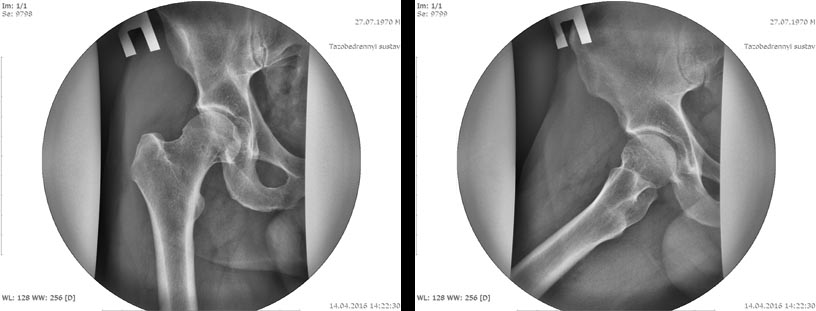

Rg

|

скорее всего причина кист - импинджемент